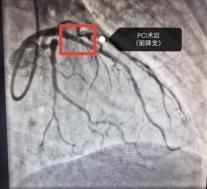

近期,六安市中医院心内科因心梗入院的患者接连不断,12月19日一天就收治了5名急性心肌梗死的患者因病情危重,其4名均急诊冠脉介入干预治疗。急性心梗如此凶险,而且冬天又是心梗高发的季节,我们应该如何预防呢?